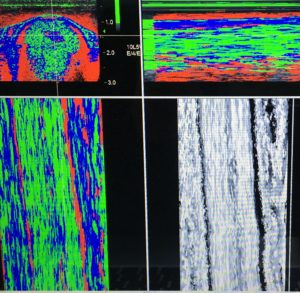

Ultrasound Tissue Characterisation (UTC) technology can differentiate between 4 different fibre types. This enables us to see how many healthy aligned fibres are present, the degree of scar tissue, the severity of a lesion, and the effect of current exercise level on the tendon, all in one scan. This information is essential for preventive screening of tendons (such as prepurchase examinations), pre-race assessments, and post-injury “staging” of the injury to guide rehabilitation.